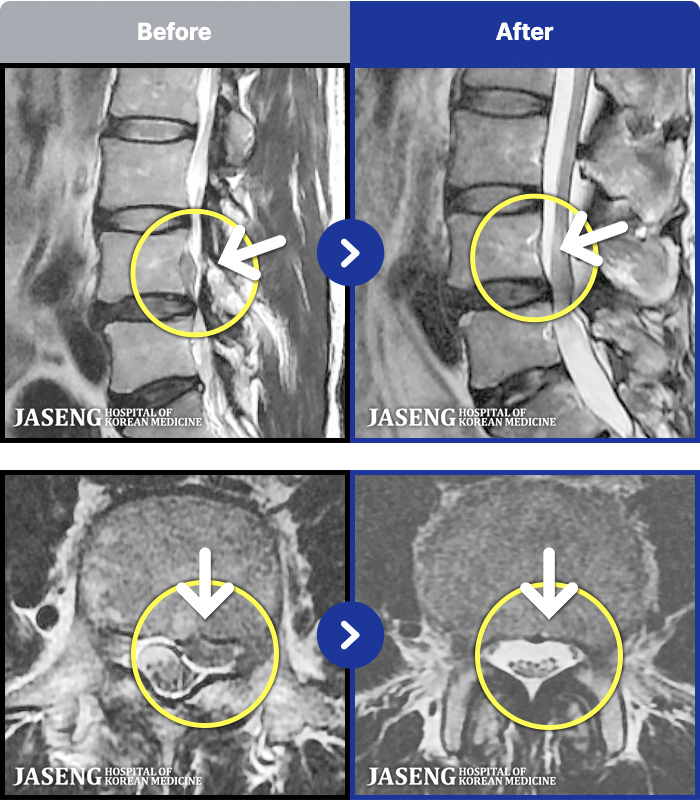

MRI ġ

54 MRI ũ ʸ Ȯϼ.

[_㸮ũ] Ͽ ü Ÿ Ͽϴ.